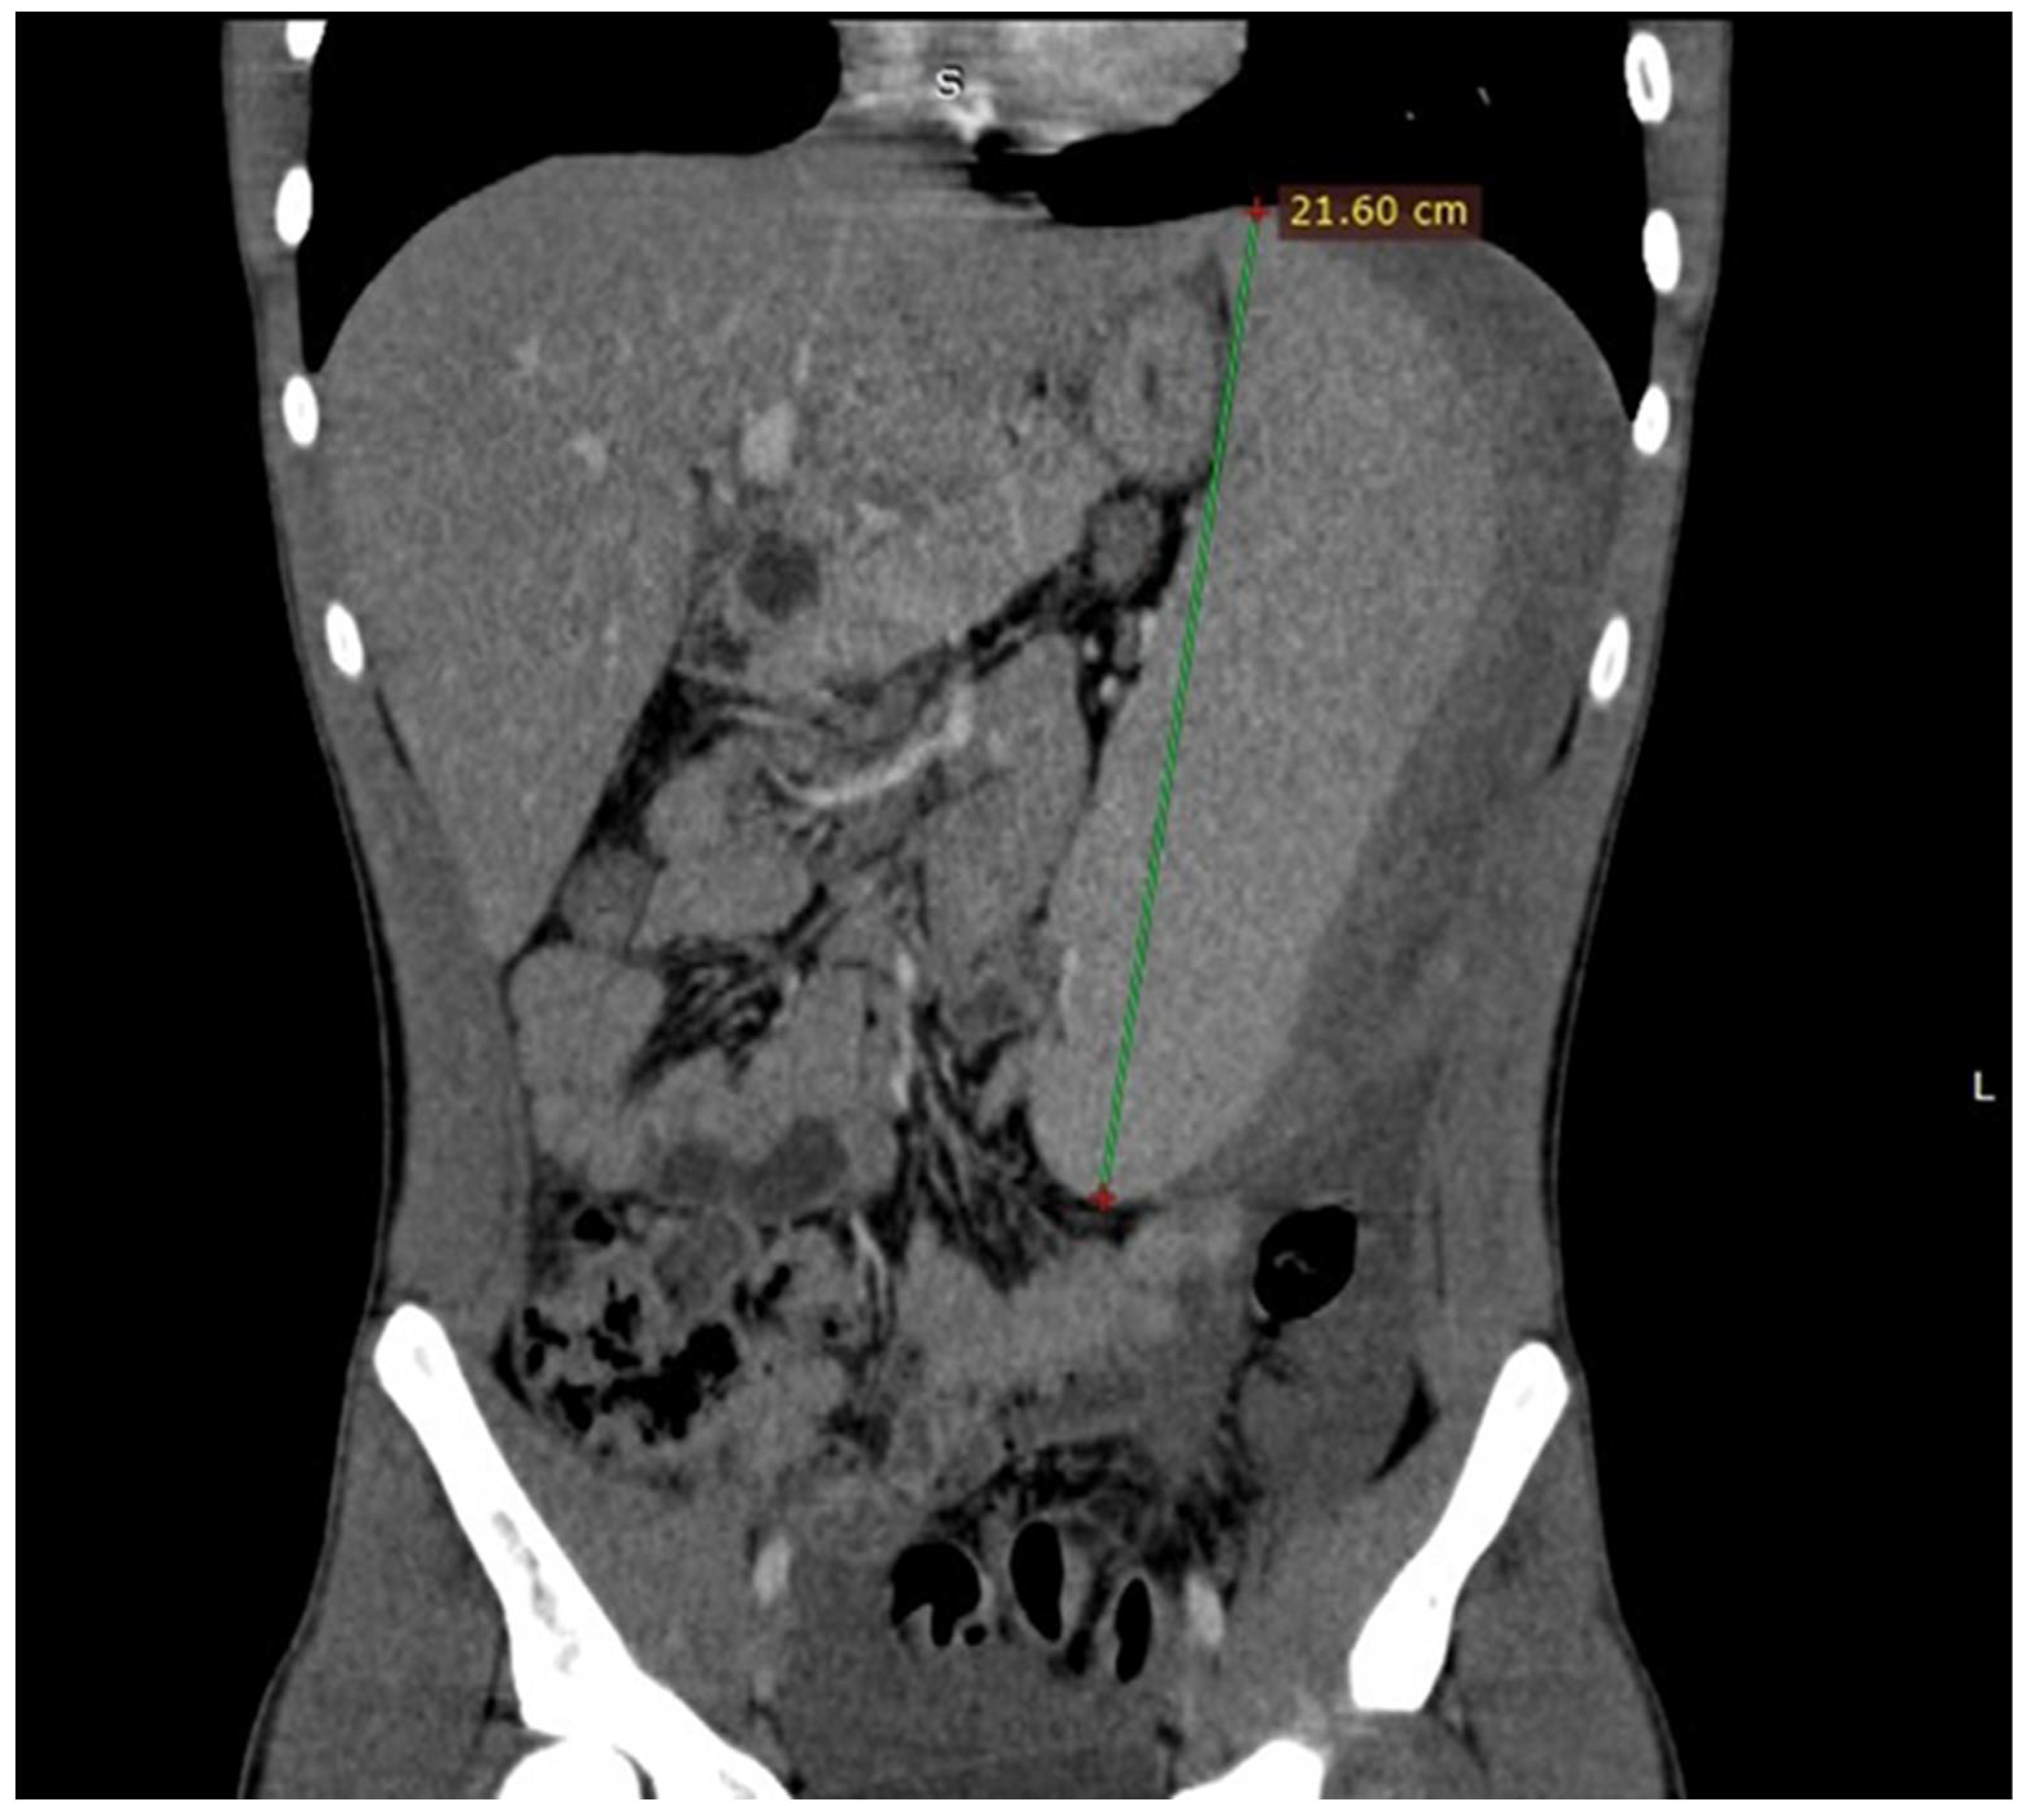

An urgent abdominal ultrasound was performed that revealed an enlargement of the spleen (21 cm of diameter) with a large subcapsular hematoma (13 cm of diameter) and a significant amount of complex fluid within the abdominal cavity. In addition, and with the patient remaining hemodynamically stable, an abdominal Computer Tomography scan was performed and the enlargement of the spleen with maximum diameter of 21, 60 centimeters(cm) and the subcapsular hematoma were confirmed.

Computer Tomography of the patient showing the enlargement of the spleen with maximum diameter of 21,60cm and the large subcapsular hematoma. The multidetector CT allows the detection and safe characterization of spontaneous splenic lesions, together with the identification or exclusion of active hemorrhage, perisplenic hemorrhage, or hemoperitoneum [